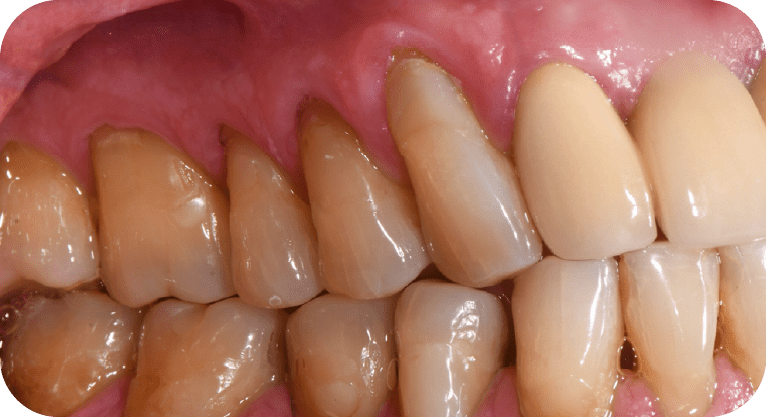

Male patient, “65” years old

Treatment: Gum surgery

The patient had dental sensitivity caused by exposed tooth roots, so a root coverage surgery with a gum gra and gum repositioning was performed. This procedure protected the exposed roots, reduced hypersensitivity, and improved both periodontal function and aesthetics, achieving satisfactory results for the patient.